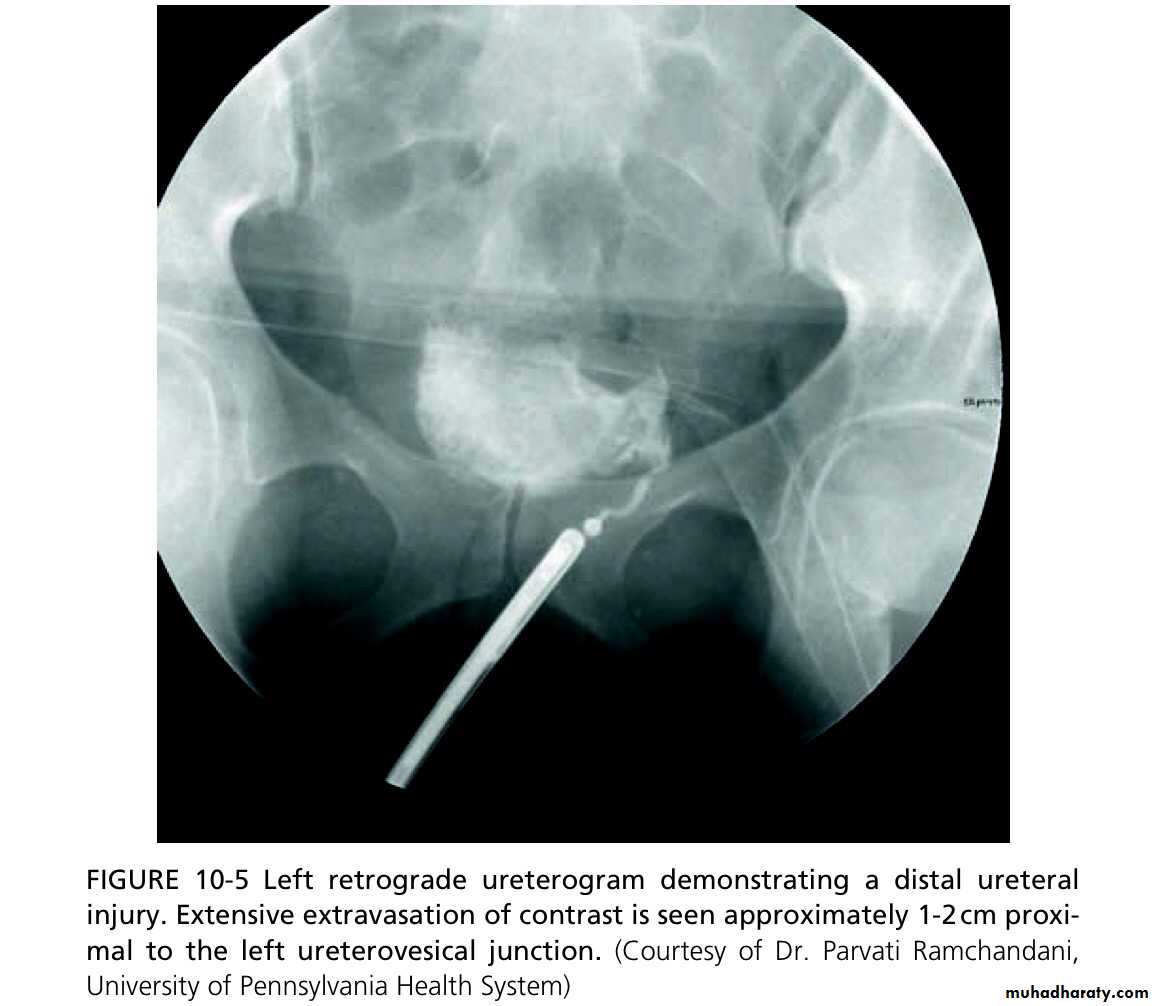

IVU or retrograde ureterogram. Ultrasonography may demonstrate hydronephrosis, but hydronephrosis may be absent when urine is leaking from a transected ureter into the retroperitoneum or peri- toneal cavity. The IVU usually shows an obstructed ureter or occasionally, a contrast leak from the site of injury.

1-JJ stenting for 3–6 weeks (e.g. ligature injury recognized immediately).

2-Primary closure of partial transection of the ureter.

3- Direct ureter to ureter anastomosis (primary uretero- ureterostomy)—if the defect between the ends of the ureter is of a length where a tension-free anastomosis is possible.

4-Reimplantation of the ureter into the bladder (uretero- neocystostomy), either using a psoas hitch or a Boari flap.